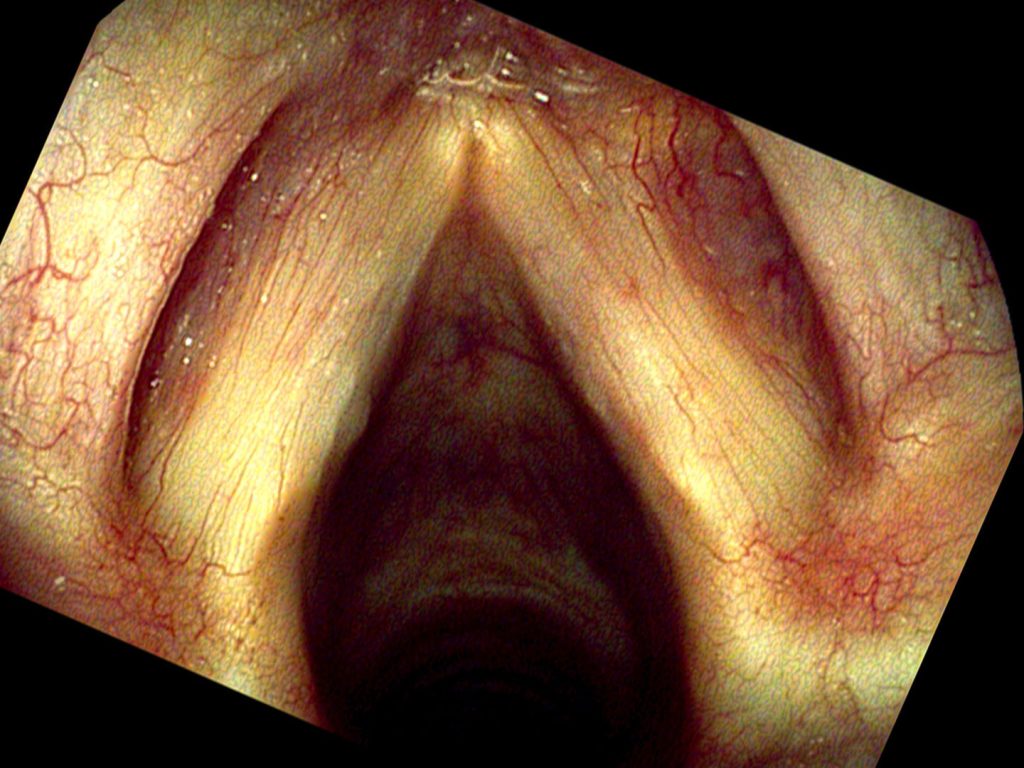

Πριν από την έναρξη οποιασδήποτε θεραπείας πραγματοποιείται ενδοσκόπηση του λάρυγγα από την μύτη ή το στόμα και καταγραφή της εικόνας για τη σύγκριση μετά την θεραπεία.

Αν αποκλειστεί η κακοήθεια, η δυσφωνία, συνήθως, μπορεί να οφείλεται σε κομβία των αοιδών (οζίδια των φωνητικών χορδών), πολύποδα της φωνητικής χορδής, ενδοχορδική κύστη της φωνητικής χορδής, θηλώματα του λάρυγγα, φωνητική αύλακα ή σχισμή (sulcus vocalis), ουλή της φωνητικής χορδής, αγγειεκτασίες των φωνητικών χορδών. Κάθε μία από τις παραπάνω καλοήθεις καταστάσεις έχει χαρακτηριστική εικόνα, που γίνεται ακριβέστερη  με τη βιντεοστροβοσκόπηση των γνησίων φωνητικών χορδών και την κυμογραφία.

Κάθε ασθενής με δυσφωνία που παρατείνεται πρέπει να παραπέμπεται για βιντεοστροβοσκόπηση. Στα παιδιά, αν η βιντεοστροβοσκόπηση είναι δύσκολο να εφαρμοστεί μπορεί να γίνει η έρευνα με εύκαμπτο ρινοφαρυγγολαρυγγοσκόπιο.